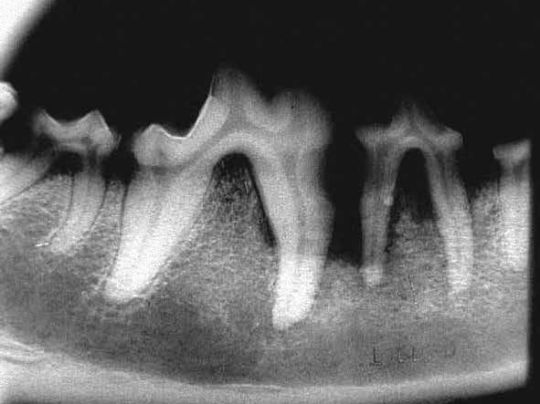

Дентальный рентген